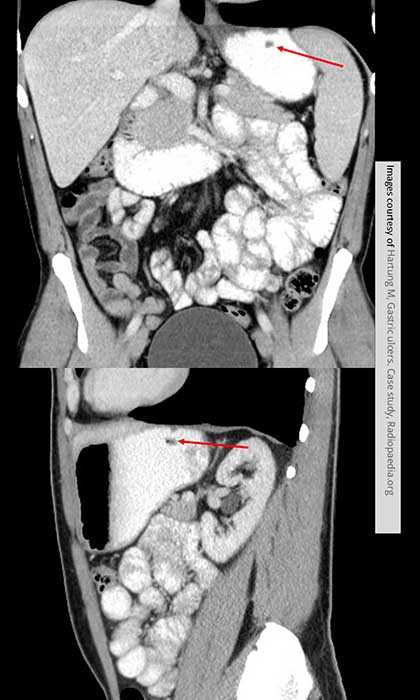

What is the radiographic appearance of infiltrative gastric carcinoma?

Thickened walls, narrowed lumen, rigid non-contracting 'fixed stomach', loss of rugal folds.

What is the hourglass stomach?

Circumferential involvement causing mid-gastric narrowing.

What is the radiographic appearance of proliferative type of gastric carcinoma?

Polypoid mass projecting into the lumen; may mimic ulcer.

What are the best imaging studies for gastric carcinoma?

UGI for detection; CT for staging, treatment, and follow-up.